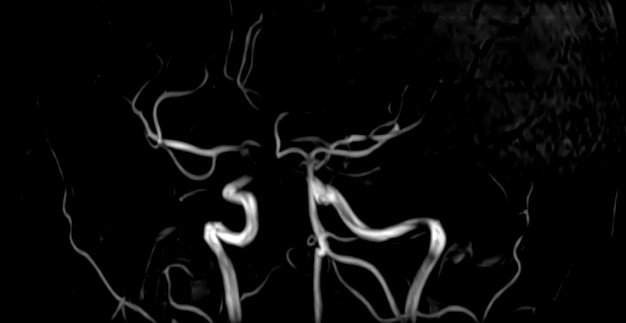

В клинике «Доступная медицина» проводится комплексное исследование: МР-ангиография шеи и головного мозга на новейшем высокопольном томографе экспертного уровня TOSHIBA VANTAGE TITAN 1,5 Тесла, который создает изображения сосудистой системы превосходного качества, что позволяет проводить точную диагностику и назначать пациенту своевременное лечение. МР-ангиография проводится в стандартном режиме без использования контраста.